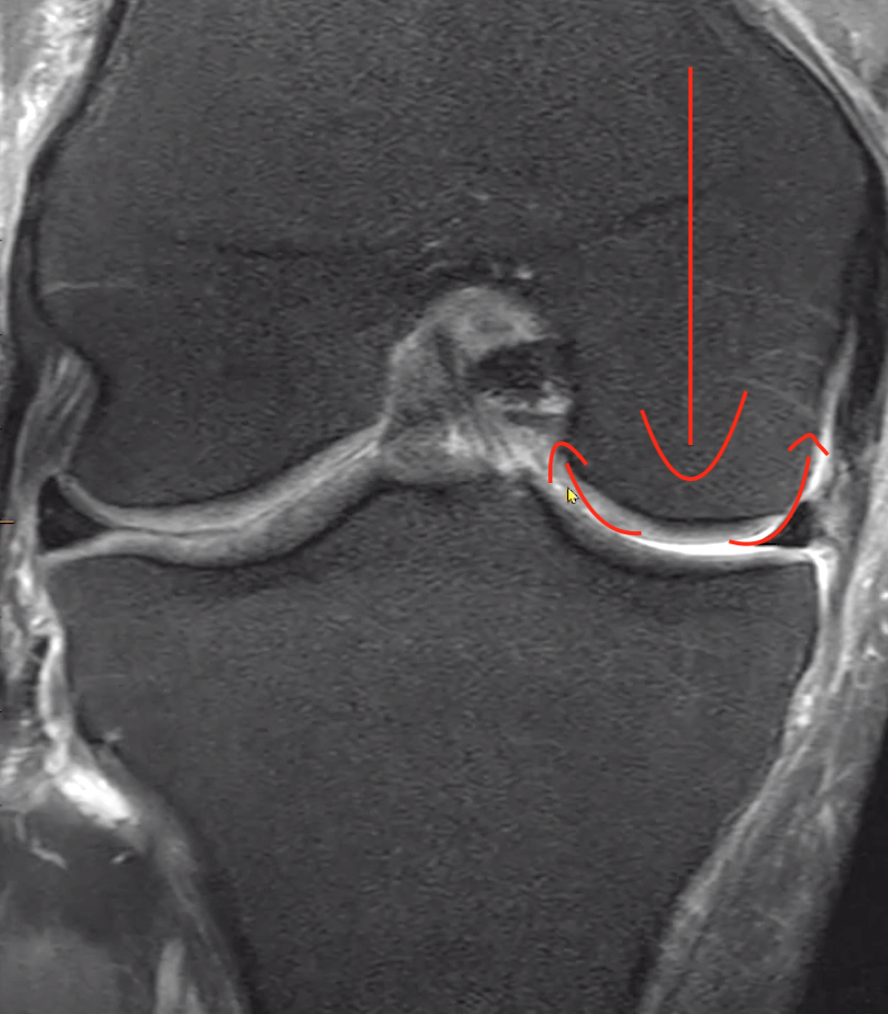

Hoop stress

• We need to think of the meniscus as a tub of toothpaste with a person squeezing the center of the toothpaste container

• When we do this the toothpaste with clump up and push out on either side of the force pushing on the center

• If the toothpaste container has the lid on then no toothpaste will spill out

• This is the same thing as the meniscus

• With the meniscus we have a piece of tissue that has a force being applied to the center of it resulting in clumping on the edges

• The central force is the femoral condyle

• The clumps of toothpaste within the jar are the meniscal triangles

• The meniscus does not get forced out of the knee joint because we have ligaments keeping it in place (the toothpaste does not get spilled out because the cap is on)

• The root ligaments keep it in place medially

• The menisco-femoral ligament and coronary ligament keep it in place laterally

• If these ligaments are torn then the meniscus can float around and be unstable (the toothpaste lid is off and the toothpaste has fallen out of the container)